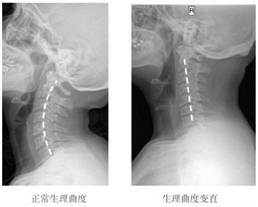

双手掰脑袋直接会"掰直"了颈椎原本有的正常生理弯曲,不仅脖子痛,甚至可能导致颈椎"变直"……

我们可以看看颈椎病患者的X光片